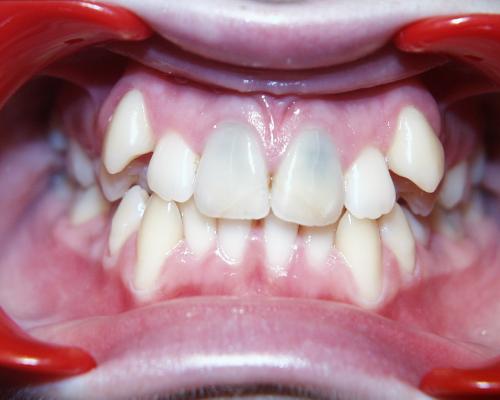

Mundfotos im Vergleich

Vor und nach der Zahnverbreiterung